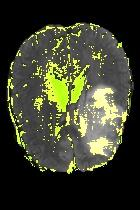

Current unsupervised anomaly localization approaches rely on generative models to learn the distribution of normal images, which is later used to identify potential anomalous regions derived from errors on the reconstructed images. However, a main limitation of nearly all prior literature is the need of employing anomalous images to set a class-specific threshold to locate the anomalies. This limits their usability in realistic scenarios, where only normal data is typically accessible. Despite this major drawback, only a handful of works have addressed this limitation, by integrating supervision on attention maps during training. In this work, we propose a novel formulation that does not require accessing images with abnormalities to define the threshold. Furthermore, and in contrast to very recent work, the proposed constraint is formulated in a more principled manner, leveraging well-known knowledge in constrained optimization. In particular, the equality constraint on the attention maps in prior work is replaced by an inequality constraint, which allows more flexibility. In addition, to address the limitations of penalty-based functions we employ an extension of the popular log-barrier methods to handle the constraint. Comprehensive experiments on the popular BRATS'19 dataset demonstrate that the proposed approach substantially outperforms relevant literature, establishing new state-of-the-art results for unsupervised lesion segmentation.